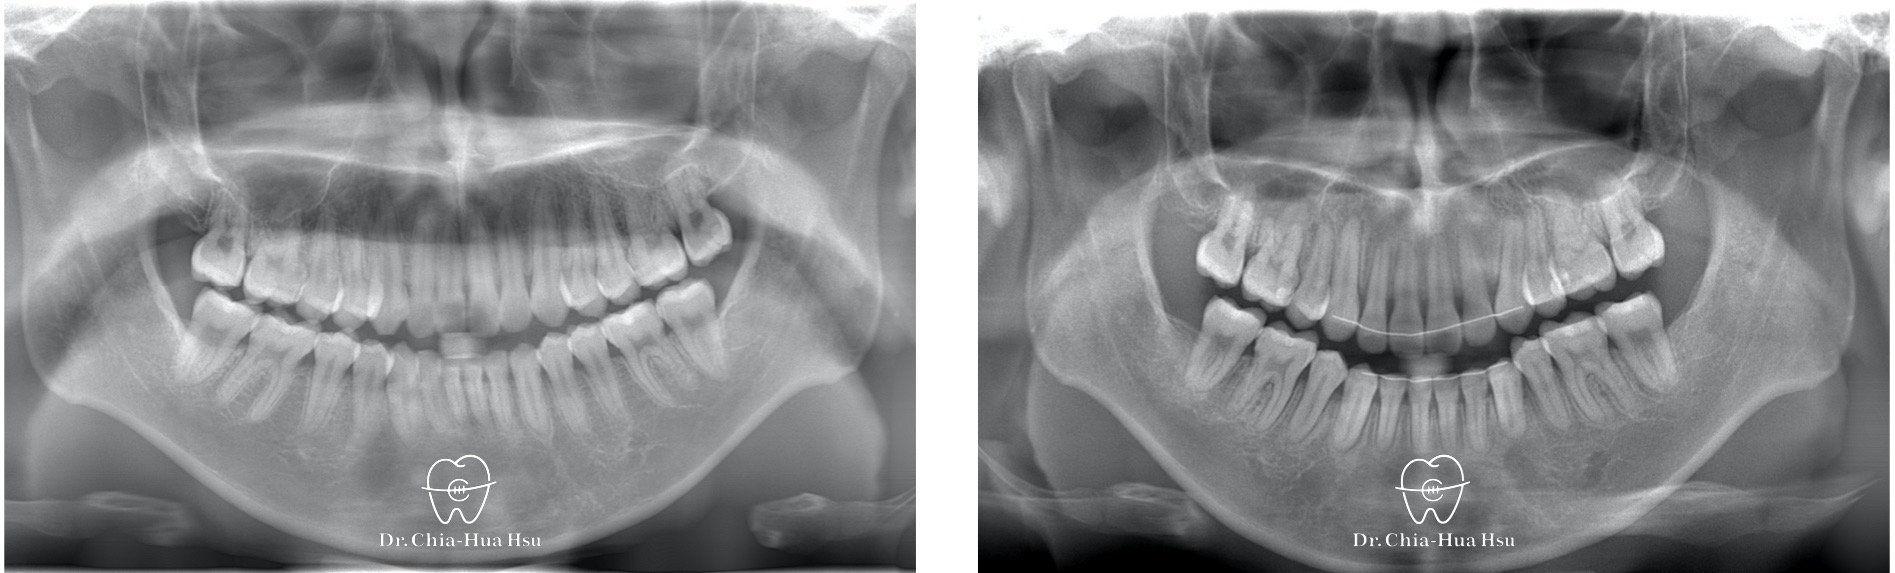

治療前

治療後

- 問題分析:患者是嚴重的骨骼二類咬合(Skeletal Class II)、下巴後縮、暴牙以及齒列不整齊。

- 治療方式:使用傳統金屬矯正器,並拔除四顆小臼齒,配合多支暫時性迷你骨釘來完成治療。